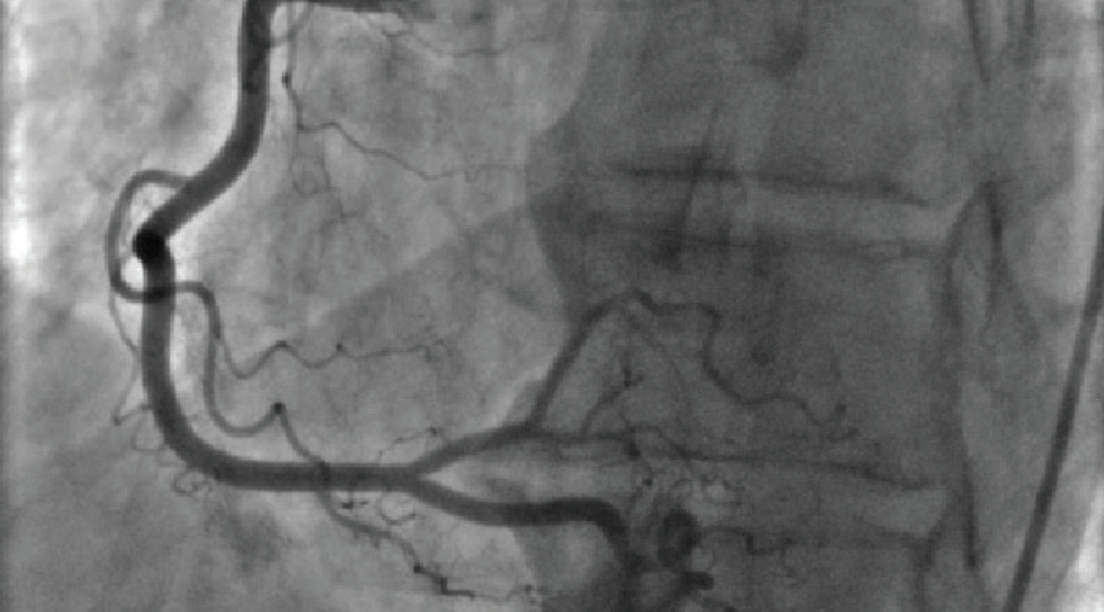

This series includes case reports involving conditions relating to cardiometabolic disease.